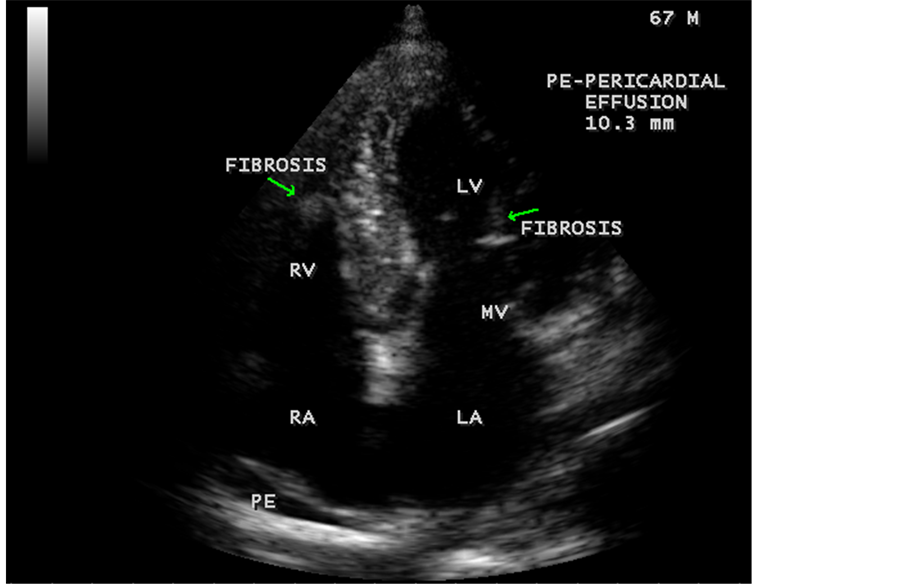

Figure 44. Showing mild pericardial effusion is an initial manifestation of Endomyocardial fibrosis in a 67-year-old male.

Figure 45. Endomyocardial fibrosis showing thickening of LV tendons seen as fibrous ridges as an initial manifestation of LV EMF in a 23-year-old male.

Today echocardiography is used as the screening tool at the community level as the diagnosis of EMF could be confirmed at the bedside. Echocardiography accurately assesses the pathological abnormalities of chronic disease and it is the gold standard technique for the diagnosis of EMF [36] . It reveals dense endomyocardial echocardiograms along different parts of the mural and valvular endocardium and AV valve dysfunction [37] as shown in Figure 3 to Figure 7, Figure 10 to Figure 15, Figure 17, Figure 18, Figure 20 to Figure 75 and Figure 78 to Figure 84. The typical feature of EMF is the obliteration of trabecular portion of the ventricle and in advanced cases, there is shrinkage of the cavities creating an apical notch, regurgitation, slow flow with spontaneous echo contrast as in Figure 36 and considerable pericardial effusion. Similar to apical notch of right ventricle, a right atrial notch is well seen as contraction (or retraction) of tricuspid annulus as in Figure 41 and right atrial notch as in Figure 42 and Figure 43, indicating the retraction of right atrial cavity as a peculiar feature of right ventricular EMF. Biventricular enlargement as shown in Figure 41 and biatrial